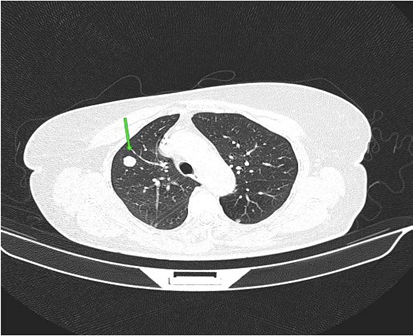

On palpation, there was an 8cm nodule in the right breast and mobile and fibroelastic axillary lymph nodes. There were no palpable nodules in the cervical or supraclavicular region bilaterally. A core needle biopsy was performed with an anatomopathological result of triple-negative grade 2 adenoid cystic carcinoma. Staging demonstrated two 1.1cm pulmonary nodules with soft tissue density suggesting metastasis. Abdominal tomography demonstrated liver nodules suggestive of secondary implants. The PET scan confirmed uptake in the lung and liver nodules, in addition to lytic lesions in S3. Liver biopsy confirmed implantation of adenoid cystic carcinoma. The patient was staged as T2N0M1. Chemotherapy was started with a regimen of Carboplatin, Paclitaxel and Pembrolizumab. After the third cycle of chemotherapy, the breast was reevaluated without showing any tumor reduction. The metastases also did not regress, and treatment was interrupted. The patient evaded the service until he returned in January 2024 complaining of pain in his right hip and difficulty walking. Chest and hip tomography showed an increase in lung lesions and the appearance of lytic metastasis in the iliac bone (figure 1, 2, 3).

Figure 1: